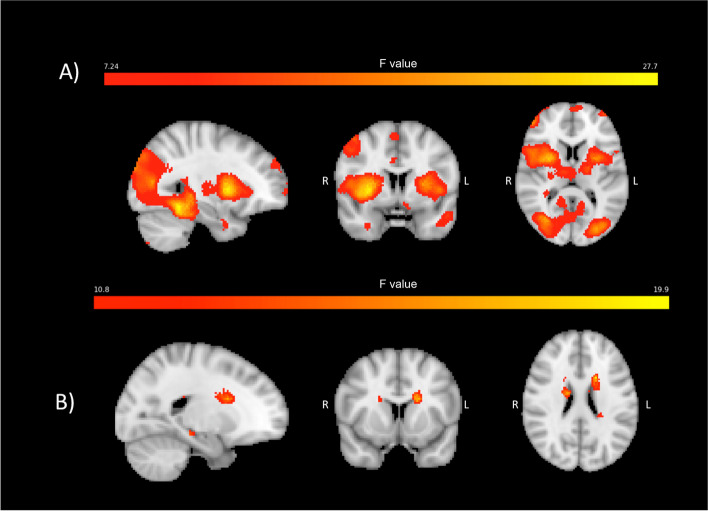

Pain-induced brain activations

The main effect of painful heat stimulation to the left forearm at the baseline visit is demonstrated in Fig. 2. This main effect demonstrates activation of ‘pain matrix’ regions, i.e., those brain regions that have consistently shown to be activated by painful stimulation and provides evidence that the pain stimuli resulted in the expected brain activations.

Fig. 2.

Main effect of painful heat applied to the left forearm at baseline (i.e. pre-treatment). A) immediate BOLD response to painful stimulation (measured starting with the MRI frame during which the painful heat stimulus began and ending 12.5 s later). B) delayed BOLD response to painful stimulation (measured starting 12.5 s after onset of painful heat stimulus and ending 12.5 s later). Hotter colors represent stronger activation